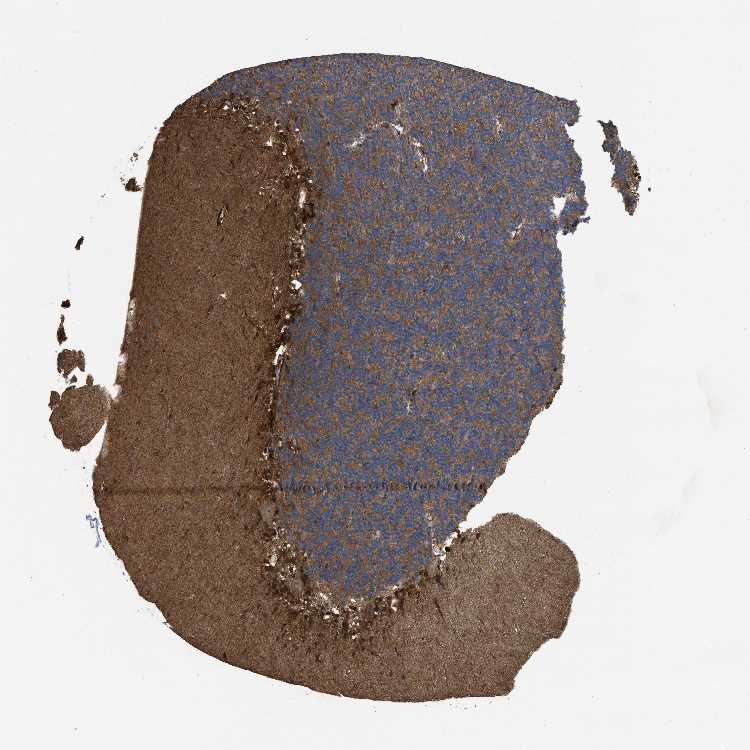

CEREBELLUM - Antibody stainingi

Antibody staining in the annotated cell types in the current human tissue is reported as not detected, low, medium, or high, based on conventional immunohistochemistry profiling in selected tissues. This score is based on the combination of the staining intensity and fraction of stained cells.

Each image is clickable and will lead to virtual microscopy that enables deeper exploration of all samples and also displays staining intensity scores, fraction scores and subcellular localization as well as patient and tissue information for each sample.

Antibody HPA018434

Purkinje cells Low

Cells in granular layer Medium

Cells in molecular layer Medium